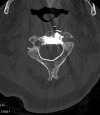

Pathologic fractures involving the C2 vertebral body and odontoid process pose a unique dilemma, as the surgical approach for direct odontoid process screw fixation has several limitations. There have been a small number of transoral approach C2 vertebroplasty or kyphoplasty reported in the literature. Previous attempts were performed utilizing fluoroscopy or CT guidance. We report a case of a fluoroscopically guided transor-al approach vertebroplasty in a patient with a lytic lesion involving the C2 vertebral body, extending into the odontoid process with an underlying pathologic fracture. This case is unique as two separate punctures were required in order to adequately stabilize the pathologic fracture, CTA was performed preoperatively to better evaluate regional vasculature, and a post-procedure rotational flat panel CT was performed to assess cement placement.